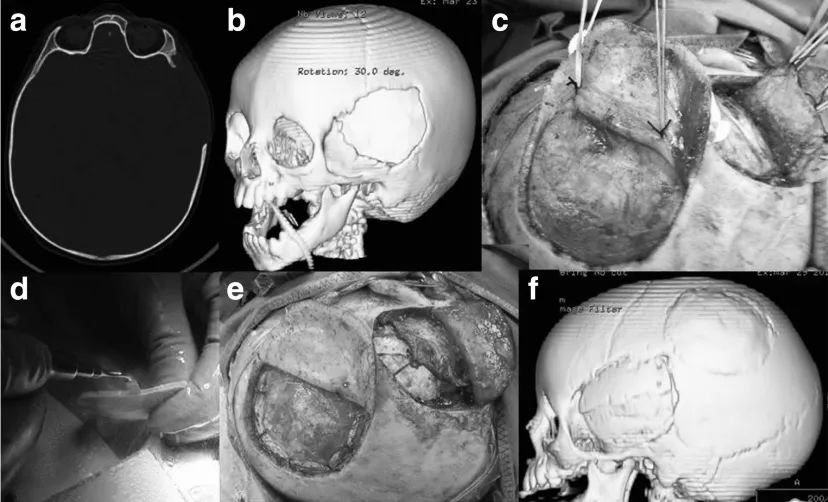

图 1:一名 11 岁女孩遭受严重头部损伤,接受右侧脑半球去骨瓣减压术(a - c),并在初次手术 20 天后进行自体骨瓣替换(d、e)。在 3 年随访中,神经状况良好(格拉斯哥结果量表 GOS 5 分),颅骨成形术成功(f)。